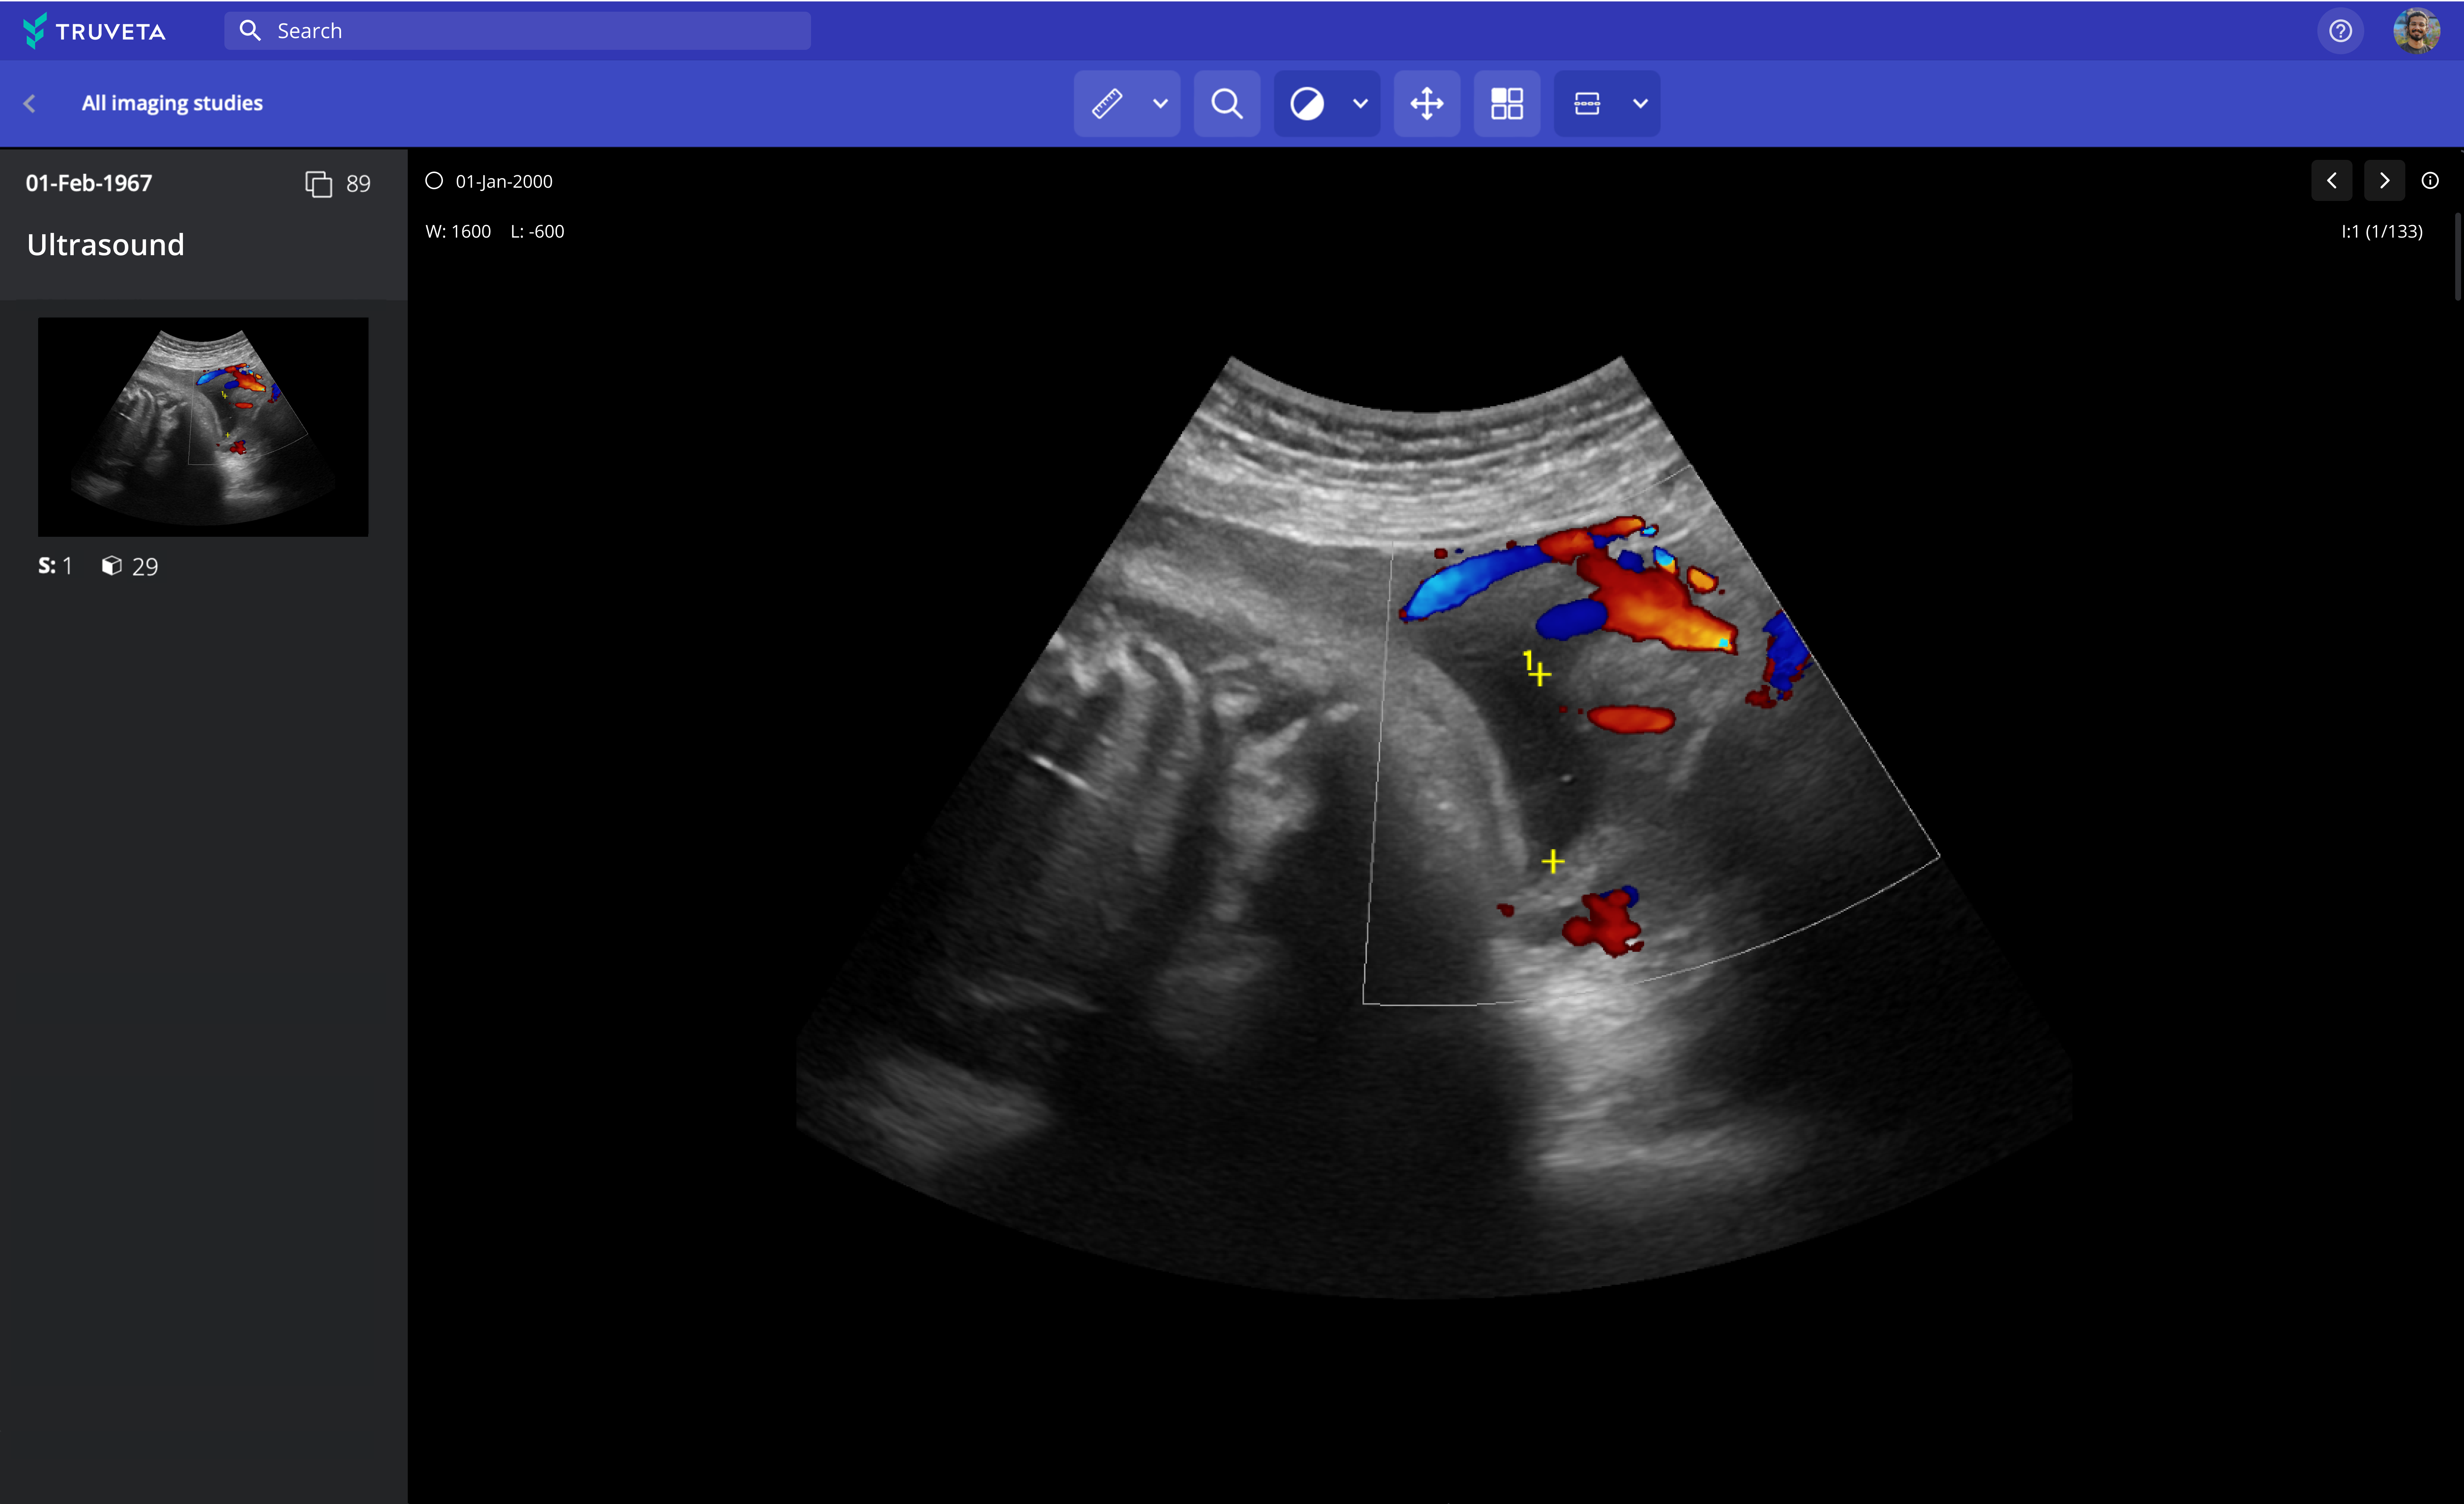

Explore images across modalities and therapeutic areas

Truveta provides pixel data and imaging metadata including MRI, CT, X-ray, ultrasound, mammogram, PET, and nuclear medicine, searchable by modality and protocol.

Accelerate research with integrated analytical tools

Truveta Studio enables researchers to preview images and easily annotate using built-in tools.

Research using echocardiography doppler for machine learning

De-identified images can be analyzed in notebooks in Truveta Studio and exported for studying imaging-based outcomes and observations, AI/machine learning model development, or inclusion in publications.